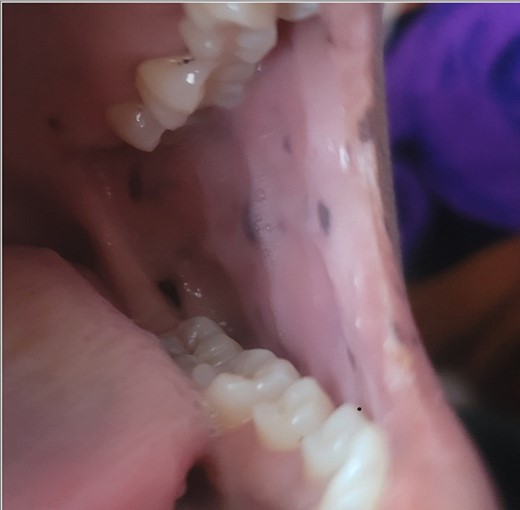

A 28-year-old female patient arrived at the emergency department complaining of intermittent colicky abdominal pain and presenting with tachycardia. She had not passed stool or flatus for 3 days, accompanied by vomiting. Upon physical examination, mucocutaneous hyperpigmentation was observed in the oral cavity (Fig. 1), along with a distended abdomen and increased bowel movement, which were hypertympanic on percussion. Initial investigations, including abdominal and pelvic ultrasonography, abdominal X-rays in erect and supine positions (Fig. 2), chest X-ray and computed tomography scan, revealed a 3-cm diameter, a 5 air level fluid, a U-shaped distension with 3.2-cm diameter mural thickening, mesenteric fat infiltration, and pneumatosis. There were no signs of peritonitis, and laboratory values fell within normal limits.

PJS is an inherited disorder characterized by multiple distinctive polyps in the gastrointestinal tract, often accompanied by mucocutaneous pigmentation, particularly noticeable around the lips. It is inherited in an autosomal dominant manner, attributed to mutations in the STK11 (LKB1) gene [8].